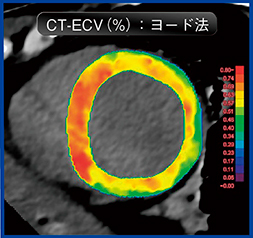

CT遅延造影の画像を使用することで,ECVの評価が可能であり,心臓MRIのECVと同等の結果を得ることが期待できる。ECVの算出法には,通常のsingle energy CTで実施可能な心筋造影効果に基づいたサブトラクション法と,dual energy CTでのヨード密度値に基づいたヨード法があり,いずれも同等の値を示すとされる5)(図4)。ECV評価は潜在性心アミロイドーシスの検出に特に有効であり,心アミロイドーシス診療ガイドラインでも紹介されている(図5,6)。Ziostation2は,サブトラクション法とヨード法のいずれにも対応している(ヨード法はW.I.P.)。

図4 心臓CTによるECV評価:サブトラクション法とヨード法

図6 心臓CTによるECV評価(ヨード法):心アミロイドーシス

dual energy CTのヨード法でECV解析を実施し,ECVが著明高値(カラーマップの赤領域)を示した。その後,心アミロイドーシスの診断に至った。